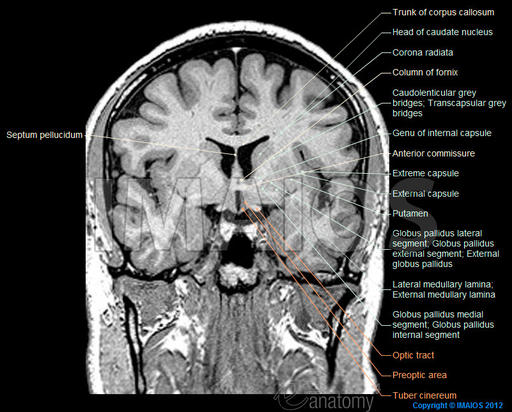

Existen herramientas de navegación digital de amplia capacidad como este atlas cerebral que permite navegar on line, gracias al etiquetado de más de 524 estructuras en 353 imágenes de resonancia magnética en los tres puntos de vista diferentes y en 26 diagramas anatómicos.

Este navegador es de Imaios y se puede navegar en modo libre – gratis o en modo de pago. La anatomía correlacionada de cabeza – cara y cuello está dirigida para el uso de profesionales con interés en la neuroanatomía y las imágenes médicas; tiene un uso adecuado para médicos generales y especialistas en neurología, neurocirugía, así como patólogos del habla y terapeutas de la psicomotricidad.

Un equipo de Resonancia Magnética realizó cortes de 0,6 mm en individuos sano, y usando ponderación T1 sin inyección de gadolinio para obtener imágenes volumétricas para la navegación 3D, con una matriz de 320/320 píxeles, utilizando una potencia de 1.3 Tesla MRI.

Las estructuras del cerebro humano se han clasificado en grupos y subgrupos que se pueden mostrar de forma selectiva en el navegador.

Las estructuras anatómicas están traducidos desde la terminología anatomica en Inglés, francés, español, portugués, checo, alemán, chino y japonés.